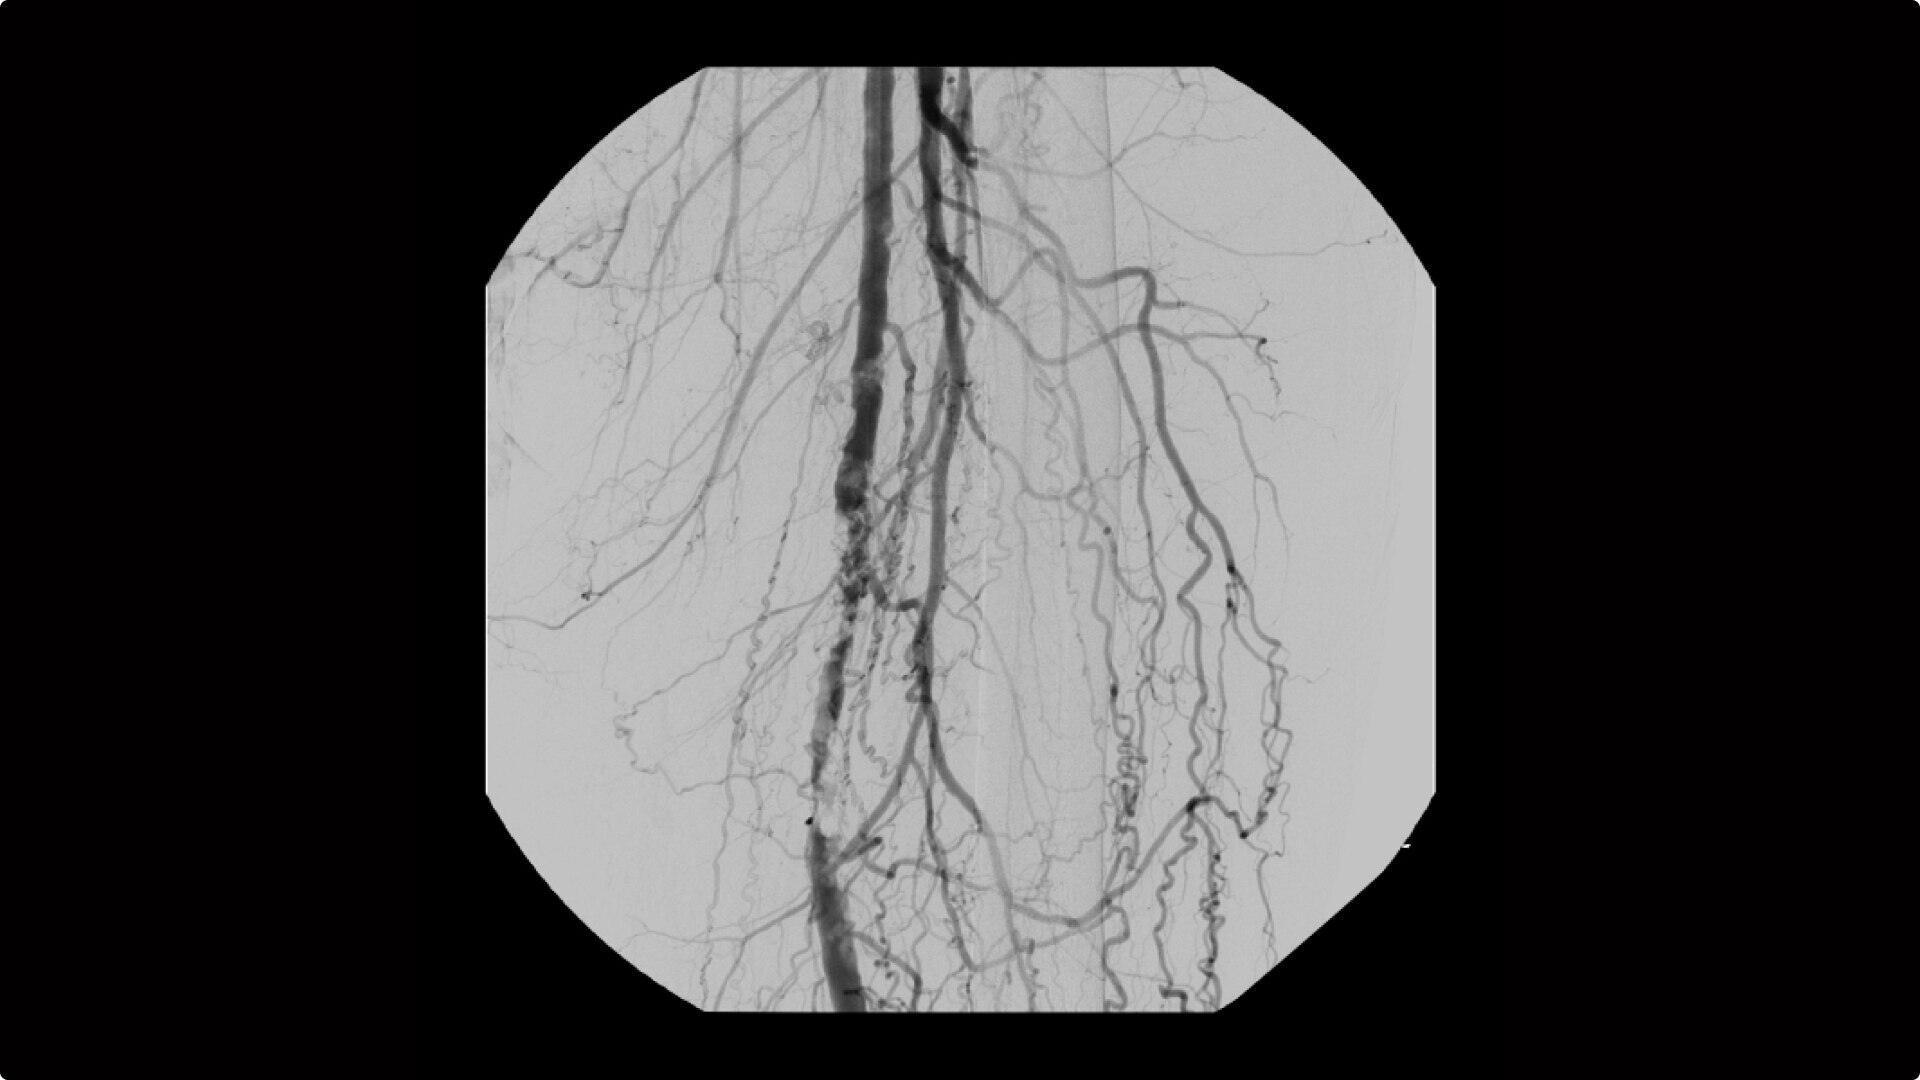

OEC C-arms are used by interventionalists and surgeons to obtain vascular imaging during peripheral to contrast run-off procedures. Superb resolution, even in the presence of motion, enables easy identification of anatomical landmarks and the extremity of the catheter, even as catheter tip moves.

Clearly see 0.014” guidewires in chest and abdomen region or 0.008” guidewires in peripheral vascular with the OEC Elite CFD with a flat detector, image processing advancements and 4K viewing display.

Perform a full leg Bolus Chase in one contrast run with a Preset Profile that includes Motion Tolerant Subtraction, that dynamically adjusts image quality based on presence of motion.

During contrast run-off procedures, easily select contrast type with positive (e.g. Iodine) or negative (e.g. Carbon Dioxide) during subtraction. The OEC Elite CFD cardiovascular package also includes Roadmapping.